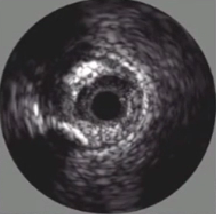

3、动脉血管IVUS基本图像

正常动脉IVUS截面上有什么呢?

1、血管外膜层: 回波密集,纤维蛋白和胶原蛋白;

2、血管中膜层: 无回波层,平滑肌细胞;

3、血管内膜层: 回波相对密集;

4、管腔: 血液;

5、盲区: 导管;

两个边界:①中膜层,连续的无回声;②血流,低回声,闪烁 流动区域;中间(3)即为斑块.